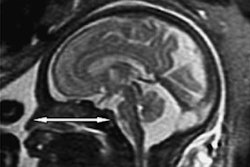

Researchers from France have used 3D MRI to visualize changes to the shape of the fetal brain and skull during the second stage of labor. The images revealed that fetal heads may experience greater stress than previously imagined, according to an article published online on 15 May in PLOS One.

The capacity of a fetus' head to change shape during the second stage of labor, or fetal head molding, is well known but hardly ever examined with medical imaging. Having a better understanding of this process could facilitate childbirth and help clinicians determine the need of an otherwise healthy patient to undergo a Cesarean delivery (C-section), noted first author Dr. Olivier Ami from the University of Clermont Auvergne, Clermont-Ferrand, and colleagues.

In the prospective study, Ami and colleagues acquired open-field 1-tesla MRI scans of 27 pregnant women before labor; seven of the women were scanned again during the second stage of labor (no more than 10 minutes before beginning expulsive efforts). Then the researchers transformed the MRI scans into finite element 3D reconstructions using proprietary 3D imaging software (Predibirth).

3D finite element reconstruction of the cranial bones before labor and during the second stage of labor. Image courtesy of Dr. Olivier Ami."During vaginal delivery, the fetal brain shape undergoes deformation to varying degrees depending on the degree of overlap of the skull bones," Ami said in a statement. "Fetal skull molding is no more visible in most newborns after birth. Some skulls accept the deformation (compliance) and allow [for] an easy delivery, while others do not deform easily (noncompliance)."

Despite normal pregnancies, two of the patients had to undergo a C-section because the heads of the fetuses turned out to be too large for vaginal delivery. These fetuses were among the three with the greatest degree of fetal head molding. For one of these cases, conventional MRI revealed that the fetal head was not ideally positioned for vaginal delivery even though a clinical exam suggested that the head was in the appropriate location.